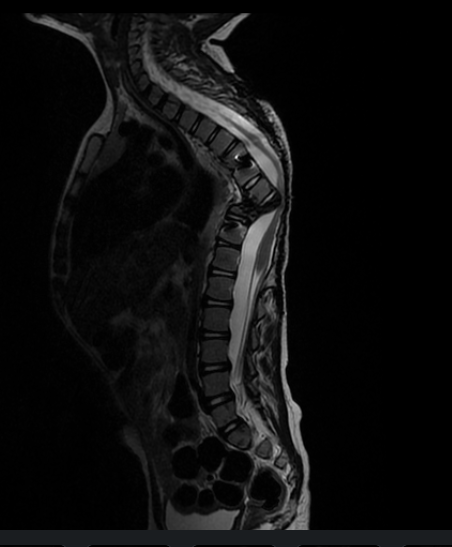

En las valoraciones iniciales, nos mencionaban que su forma de caminar podía deberse a otras causas y que podría mejorar con el uso de plantillas. Sin embargo, como papás, no nos quedamos con esa duda. Buscamos segundas opiniones y realizamos estudios más específicos RM y TAC.

During the initial evaluations, we were told that the way he was walking could be due to other causes and that it might improve with the use of orthopedic insoles. However, as parents, we could not ignore our concerns. We sought second opinions and pursued more detailed studies, including MRI and CT scans.

Today we know that Jorge Luis is facing another serious problem in his spine.

Hoy sabemos que Jorge Luis enfrenta nuevamente un problema en su columna.